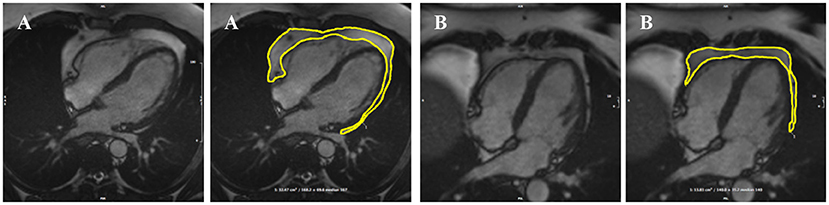

The analysis protocol comprised segmentation of an en bloc PAT area from standard four-chamber cine images (single 2D slice), a universal component of standard CMR studies and one that demonstrates less variability in cut plane positioning compared to other acquisitions (e.g., short axis slices). For consistency, we measured PAT at phase 1 of the imaging cycle (approximately end-diastole). A single contour was drawn to select areas of high signal intensity adjacent to the epicardial surface of the left and right ventricular myocardium, resulting in output of an area measure in cm2 (Figure 1). Areas of high signal intensity over the liver were not included, as this almost always represents adipose tissue below the diaphragm (Figure 1B).

Figure 1. Two examples of PAT contoured in end-diastole on four-chamber bSSFP cine-CMR, performed using CVI42® software according to the established SOP. A single contour was drawn to select areas of high signal intensity adjacent to the epicardial surface of the left and right ventricles, resulting in output of an area measure (A). Areas of high signal intensity over the liver were not included in the PAT measure as this almost always represents adipose tissue below the diaphram (B). bSSFP, balanced steady state free precession; CMR, cardiovascular magnetic resonance; PAT, pericardial adipose tissue; SOP, standard operating procedure. Images reproduced with permission of UK Biobank.